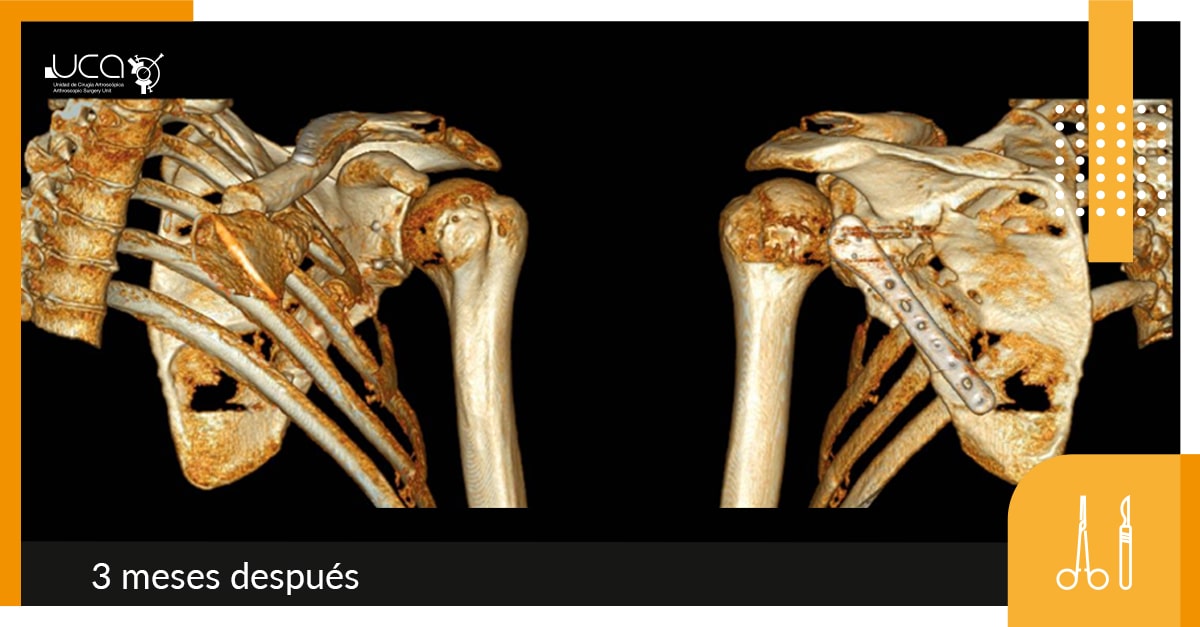

Se realiza reducción y osteosíntesis con placa de neutralización anatómica de pilar lateral.